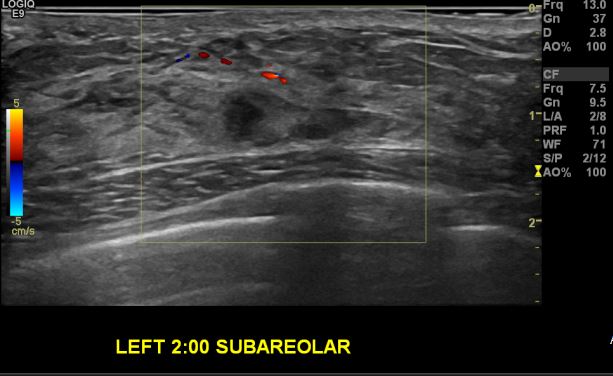

상기환자 2015.09 건강검진상 이상 소견으로 본원 경과관찰 하시는 40대 여성 분으로

좌측 2시 유두 밑 새로 생긴  0.5cm 혹 조직검사 시행하여 좌측 침윤성 유관암

진단 되었습니다.